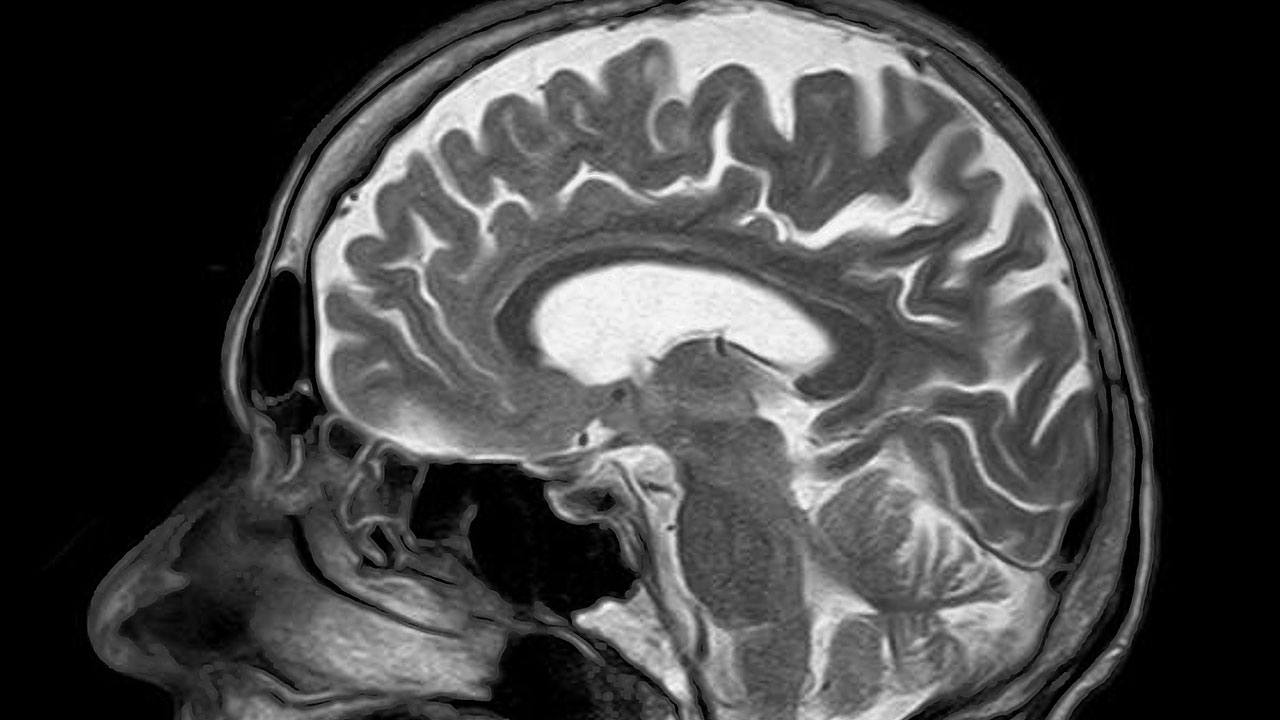

뇌에 축적된 노화 세포(일명 좀비 세포)를 제거하면 비만으로 인한 불안증을 완화할 수 있다는 연구결과가 나왔다고 유전·생명공학 전문매체 '젠(GEN; Genetic Engineering & Biotechnology News)'이 7일(현지시간) 보도했다.

노화 연구로 유명한 미국 메이요 클리닉 연구팀은 생쥐 실험에서 이 같은 사실을 새롭게 확인하고 학술지 '셀 머태벌리즘(Cell Metabolism)' 최근호에 연구 보고서를 발표했다.

연구팀은 특히 비만 상태인 사람의 뇌에 쌓인 노화 세포가 불안증을 높이면서 신경정신학적 기능에 이상을 일으킨다는 점에 착안했다.

연구팀은 노화한 뇌세포 축적과 뇌 지질 침적 사이의 연관성을 알아보기 위해 나이 든 생쥐를 모델로 실험했다.

비만과 비만으로 생기는 불안증이 어떻게 연관됐는지를 규명한다는 목적도 있었다.